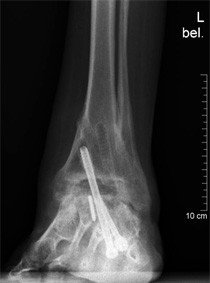

Im März 2011 erfolgte eine notfallmässige Konsultation der Patientin in unserer Sprechstunde. Sie berichtete über plötzlich aufgetretene Schmerzen im Bereich des oberen Sprunggelenkes. Es bestehe ein Hitzegefühl mit Schwellung, der Fuss sei nicht mehr belastbar. Gegen die Schmerzen müsse sie grosse Mengen an Schmerzmittel einnehmen. Ein Unfall habe sich nicht ereignet.

Klinisch zeigte sich eine Schwellung des Fusses mit Betonung der Sprunggelenkregion. Druckdolenzen finden im gesamten Rückfussbereich. Die durchgeführten Röntgenaufnahmen ergaben den Verdacht einer pseudarthrotischen Situation, was bedeutet, dass die im Jahr 2007 durchgeführte Versteifungsoperation sich vermutlich aufgrund einer neuerlichen Nekrosebildung aufgelöst hatte.

Zur weiteren Diagnostik erfolgte die Durchführung einer Computertomographie. Hier zeigt sich eine partielle Nekrose im Bereich der durchgeführten Arthrodese des oberen Sprunggelenkes. Vermutlich hat ein Teil des seinerzeit eingebrachten Knochens keinen adäquaten Anschluss an die Durchblutung gefunden und ist nekrotisiert.

Dies machte eine erneute Operation im Bereich des oberen Sprunggelenkes erforderlich. Mit der Patientin wurden die Therapieoptionen besprochen. Als einzige praktikable Lösung erscheint die Durchführung eines Debridements des nekrotisierten Bereiches und damit verbundener neuerlicher Verschraubung des oberen Sprunggelenkes.

Im März 2011 erfolgte eine erneute Operation des oberen Sprunggelenkes mit Einlage von Fremdknochen in die debridierte Defektregion. Der intraoperative optische Aspekt des Knochens zeigte ebenso wie im CT eine Nekrotisierung, die Knochensubstanz stellte sich weich dar. Zahlreiche Gewebeproben wurden während der Operation entnommen und zur bakteriologischen Untersuchung eingeschickt. Die Proben zeigten ein seltenes Keimwachstum, was eine Antibiotikaeinnahme über mehrere Monate erforderlich machte.